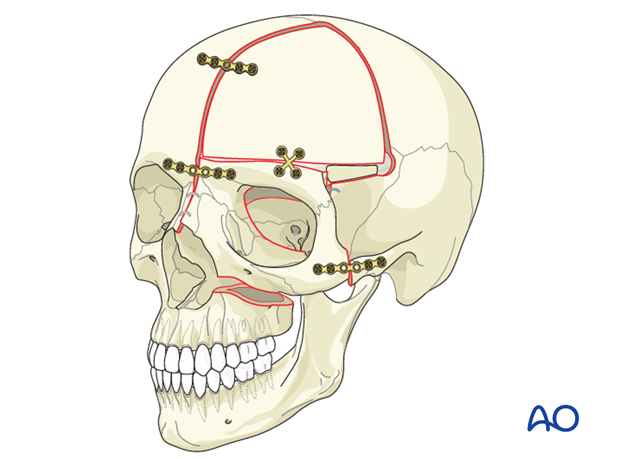

4. MSE + Facepulling *

^^ JFL at this truecel

5. Fillers

11. Jaw surgery (Chin wing, BSSO, Bimax..)

12. Surgery on midface (Lefort 1-2, 3.. Midface lift, high cut lf1)

13. Orbital box osteotomy

(Done on deformed patients only)

15. Liposuction

24. Chin wing osteotomy

11. Jaw surgery (Chin wing, BSSO, Bimax..)

12. Surgery on midface (Lefort 1-2, 3.. Midface lift, high cut lf1)

13. Orbital box osteotomy

(Done on deformed patients only)